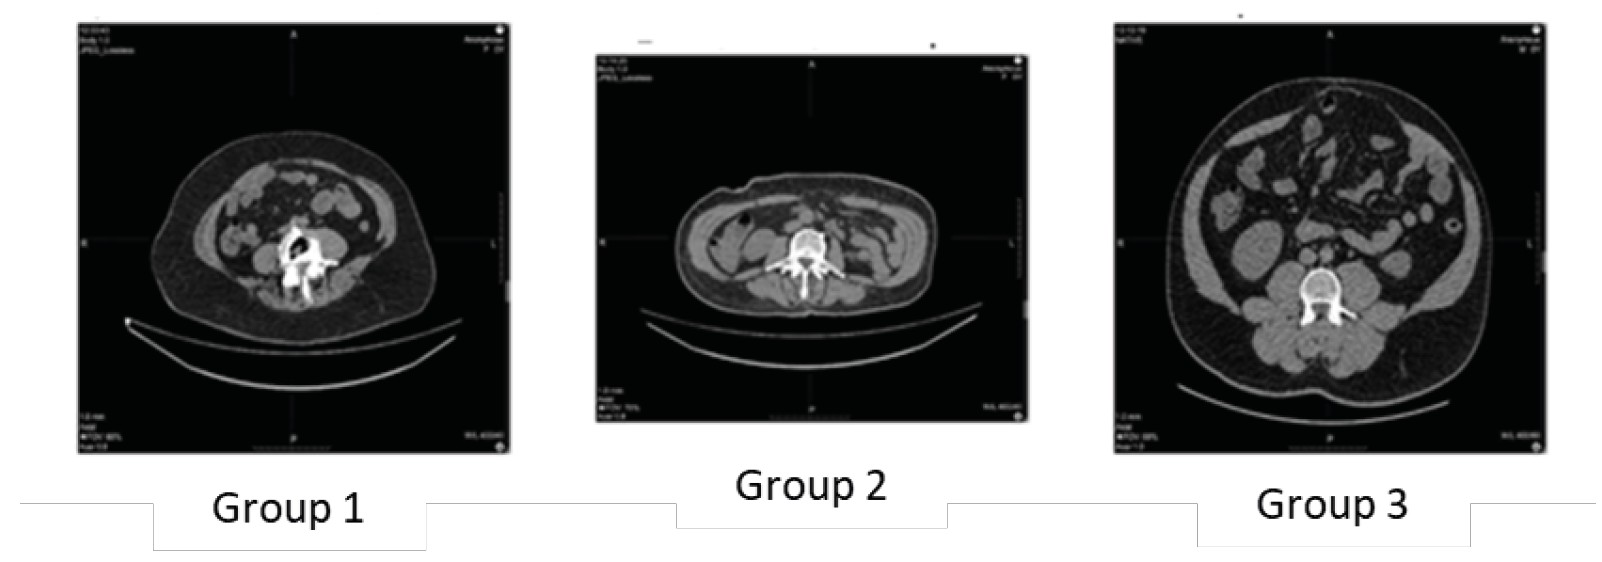

In the axial CT series, segmentation of the anterior abdominal wall muscles was performed, including the external oblique muscle (m. obliquus externus abdominis), internal oblique muscle (m. obliquus internus abdominis), and transverse abdominal muscle (m. transversus abdominis) on both the right and left sides. The segmentation of anatomical structures was carried out using the Roboflow platform (https://app.roboflow.com) through automated segmentation methods with manual correction when necessary. The U-Net convolutional neural network was used as the baseline algorithm for segmentation (Figure 2).

Fig. 2. An example of a CT scan and the corresponding mask of the musculo–aponeurotic layer of the anterior abdominal wall on the right

To enhance the accuracy of annotation, manual correction of segmentation masks was performed following automated segmentation, allowing for the minimization of errors associated with tissue heterogeneity and intensity gradient variability.